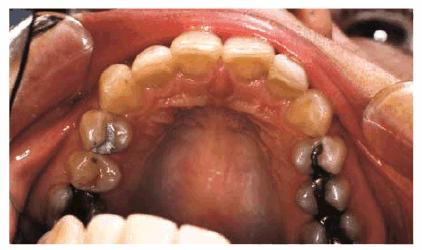

PROBLEM: This 38-year-old store owner presented with crowded and

discolored maxillary and mandibular teeth (Figures 24-7A, and 24-7B). Although orthodontic treatment was suggested as ideal

treatment, he elected a compromise that consisted of bonding the mandibular and

Figure 24-7A: This 38-year-old man wanted to improve his crowded maxillary and mandibular teeth.

Figure 24-7B: This occlusal view shows why full orthodontic treatment was originally presented as the ideal treatment. The patient insisted on a "quick fix" solution.